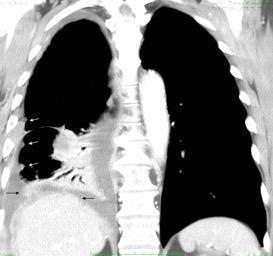

Marzo 2014: Perforación longitudinal distal secundaria a episodio de vómito (síndrome de Boerhaave). Derrame pleural izdo. que evoluciona a empiema.

Wang C-T et al. Tension hydropneumothorax in a Boerhaave syndrome patient: A case report . World J Emerg Med, 2021. Katabathina V et al. Nonvascular, nontraumatic mediastinal emergencies in adults:a comprehensive review of imaging findings. Radiographics. 2011.